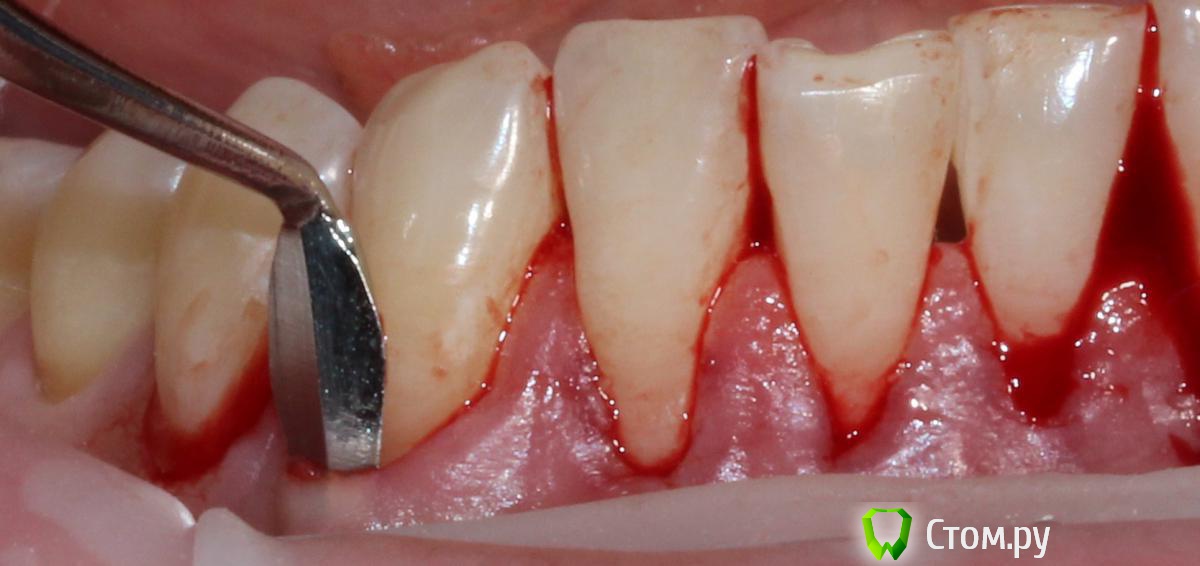

Популярный пост zzkz Опубликовано 18 сентября, 2014 Популярный пост Поделиться Опубликовано 18 сентября, 2014 (изменено) Жалобы эстетические и сильная чувствительность Рецессия от 34 до 44 Подготовка поверхности корней только скэйлинг СДТ с 2-х сторонНа небе каппа Ушивание пролен 6-0 2 недели после Чувствительности нет на сегондя. Ждать ли еще убыли или прироста? Сосочек закрыл "черный треугольник". Не уйдет ли? Изменено 18 сентября, 2014 пользователем zzkz 33 Ссылка на комментарий